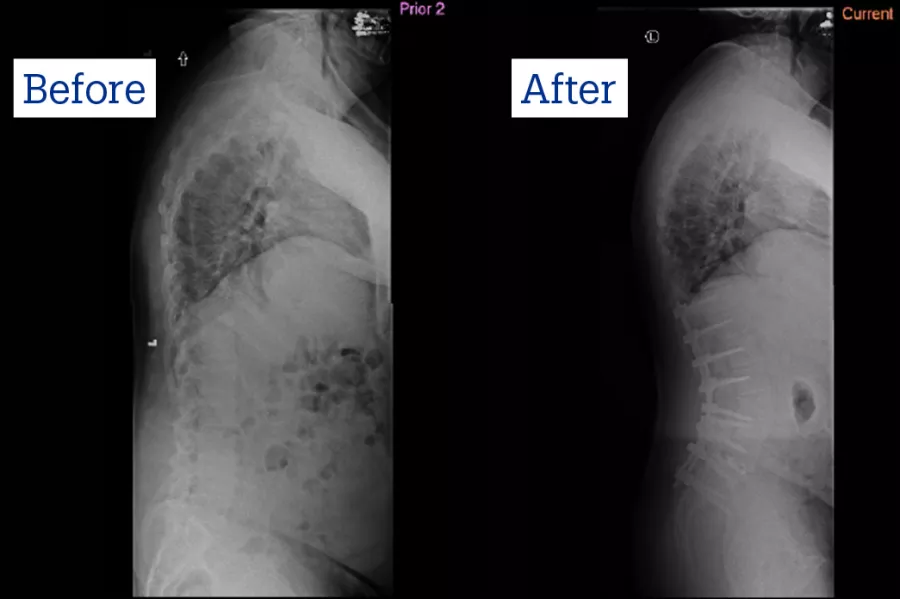

Peter Bradford couldn’t believe his eyes when Ron Riesenburger, MD, showed him an X-ray of his spine.

“I said, ‘holy cow, is that me?’”

The discs in Peter’s spine were collapsing and degenerating, which was the reason he was in tremendous pain, hunched over and leaning to the left, unable to walk 100 feet to his mailbox.

“It was bad; it looked like my spine was tipping over, and one of the vertebrae was coming out of place,” said Peter. His wife Trisha added that he was “bent over like an L” and spent his days in a recliner, unable to do anything but watch TV.

Peter underwent the surgery in May of 2020, during the height of COVID, and remained in the Intensive Care Unit for 6 days. To straighten and restore the normal curvature of the spine, Dr. Riesenburger fused vertebrae, securing the spine with rods and screws.

“The gist of it is, it’s tremendous (amount of) hardware; 3 quarters of my back is rods,” said Peter, now 71. “I can’t bend over; my posture is always correct.”